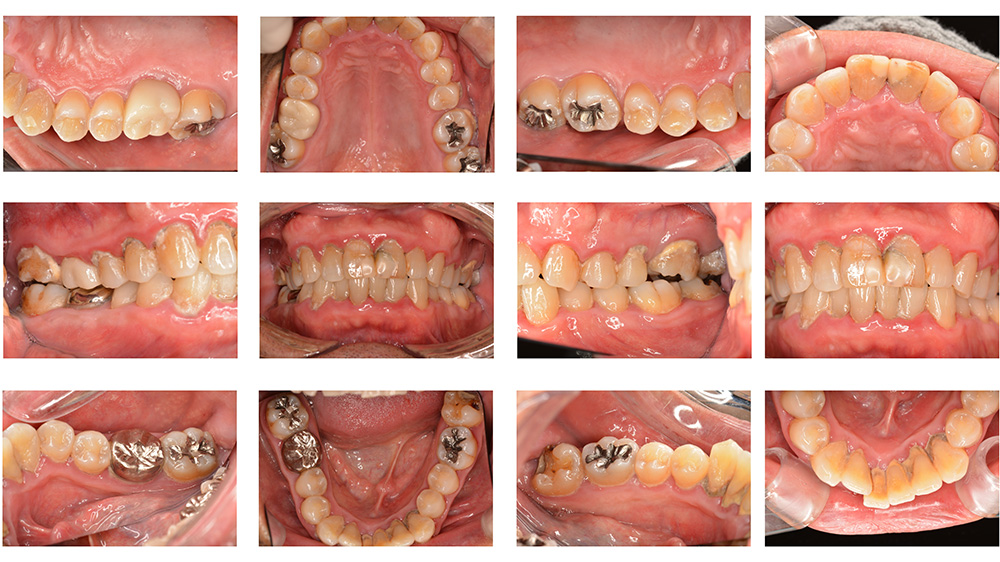

術前

術後

世代・性別

40代女性

主訴

歯が揺れている気がするので見てほしい

治療内容

ブラッシング指導、歯周基本治療

治療期間

4ヶ月

治療費

保険適応内

治療のリスク

一時的に歯ぐきからの出血や痛み、歯のしみ(知覚過敏)が起こることがある